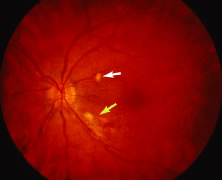

The ARN patient typically presents with progressive visual blurring in one or both eyes occurring over several weeks. These patients often are initially treated with corticosteroids, antitoxoplasmosis drugs, and other medications before arriving at the correct diagnosis. Examination reveals a prominent anterior uveitis that may be granulomatous or nongranulomatous (Fig. 1). Inflammatory signs may be prominent and cause severe pain (Fig. 2). The uveitis may be diffuse and so severe that it causes proptosis. These signs, and the diffuse vitreitis that makes the view of the retina difficult, may contribute to the high degree of delayed and/or misdiagnosis that occurs in the early stages of the disease. Significant vitreous cellular infiltration is seen in the presence of retinitis that is manifest by opacification of the retina, often most prominently in the periphery. Posterior pole involvement may include retinitis, as well as inflammation of the optic nerve head. Optic neuropathy might be the first sign of ARN with subsequent development of other retinal manifestations.8 Ultrasonography and computed tomography (CT) might be helpful in cases of ARN associated with optic nerve edema revealing enlargement of the optic nerve sheath.9 Even in ARN patients who are not immunocompromised and who have no clinical evidence of encephalitis, magnetic resonance imaging of selected cases has shown lesions of the lateral geniculate, optic tracts, and chiasma, which suggests that the virus spreads through the central nervous system (CNS) by axoplasmic transport from the retinal ganglion cells.10 A secondary retinal vasculitis is common, often accompanied by a mild number of retinal hemorrhages. Days to weeks after onset of the infection, the discrete peripheral lesions typically coalesce into a white or yellow ring of infected retina, and the associated vasculature is obliterated (Fig. 3). Necrotic retina desquamates into the vitreous resulting in vitreous sheets.3,6 Eventually, most untreated eyes can be expected to develop retinal detachment resulting from development of multiple full-thickness retinal breaks accompanied by traction or exudation.11 Giant retinal pigment epithelial tears have also been reported.12